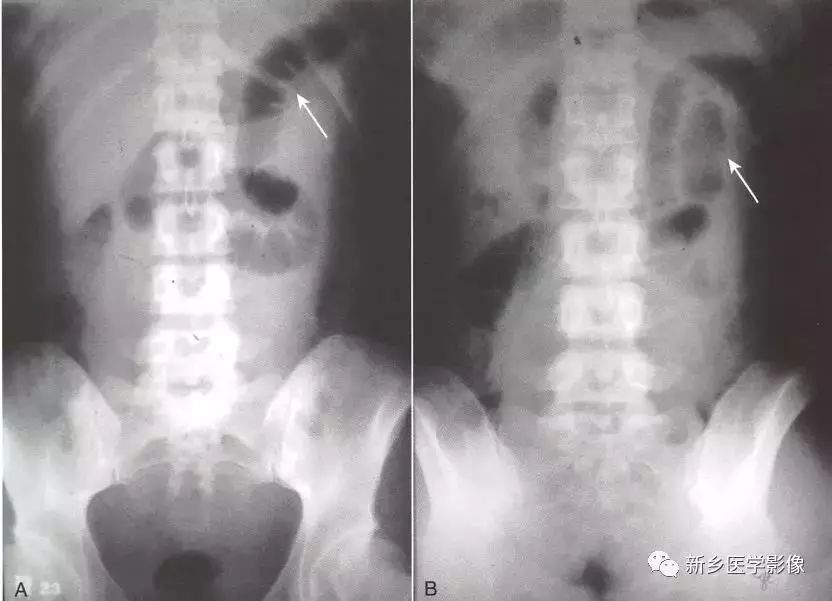

肠梗阻x线表现,绞窄性肠梗阻x线图片

绞窄性肠梗阻x线图片

肠梗阻x线表现图片

肠梗阻X线

肠梗阻x光片示意图

肠梗阻x线图片及报告

肠梗阻x线图片

肠梗阻的典型x线表现